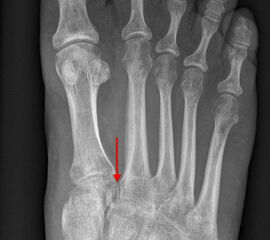

Auf den dp-Aufnahmen sollte der mediale Rand der Metatarsale-2-Basis mit dem medialen Rand des Os cuneiforme intermedium eine homogene Linie ohne Stufenbildung bilden (Abb. 7+8). Außerdem ist auf den Abstand zwischen der Metatarsale-1- und -2-Basis zu achten. Dieser sollte nicht größer als 2 mm bzw. im Vergleich zur Gegenseite nicht mehr als 1 mm erweitert sein. In bis zu 90% der Fälle zeigt sich ein sogenanntes „Fleck sign“ (Abb. 9), ein knöchernes Fragment zwischen der Metararsale-1- und -2-Basis im Sinne eines knöchernen Ausrisses des Lisfranc-Ligaments an der Metatarsale-2-Basis 211936410. Oft liegen zusätzliche Frakturen der Metatarsalebasen oder der Tarsale vor, die ebenfalls identifiziert werden sollten. Bei jeder Mittelfußbasisfraktur sollte umgekehrt an eine Lisfranc-Verletzung gedacht werden.

Zum Lesen der Bildbeschreibung und zur Vollansicht bitte die Bilder anklicken.